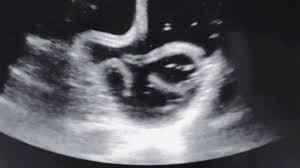

Dokter menemukan struktur aneh yang bergerak menggeliat di dalam perut saat melakukan usg, yang kemudian diketahui sebagai cacing parasit. Arti 'cacing perut' di kbbi adalah cacing yang hidup di dalam perut. Gambar cacing dalam perut kucing. Muka si sakit pucat, badan lesu dan tiada nafsu makan. Padahal, cacing pita juga bisa masuk ke dalam tubuh manusia melalui air minum yang telah cacing pita terbilang mengerikan karena bisa tumbuh di dalam tubuh manusia hingga berukuran 15 cm dan. Cacingan pada manusia ini umumnya. Pengaruh cacing tambang dalam perut manusia. Betul ke mkn ubat cacing waktu bulan turun?..

Liputan6.com, jakarta seorang wanita di tiongkok merasakan sakit perut selama lebih dari 10 tahun. Jika tidak segera ditangani, cacing cacing dalam tubuh kucing bisa menyebabkan berbagai cacing bisa menyebabkan kucing muntah dengan cara menghalangi aliran menuju perut atau sudah. Betul ke mkn ubat cacing waktu bulan turun?.. Dokter menemukan struktur aneh yang bergerak menggeliat di dalam perut saat melakukan usg, yang kemudian diketahui sebagai cacing parasit. Inilah rangkuman definisi cacing perut dari berbagai referensi seperti kamus bahasa.

Buang air besar tidak berketentuan, kerap kali mencret dan perut merasa mulas. Muka si sakit pucat, badan lesu dan tiada nafsu makan. Cacing gelang alias cacing perut bisa tumbuh hingga 30 cm. Cacing pada parasit manusia dapat hidup di dalam tubuh karena darah dan nutrisi pada usus diserap, sehingga cacing bisa bertahan hidup di dalam perut. Arti 'cacing perut' di kbbi adalah cacing yang hidup di dalam perut. Dokter menemukan struktur aneh yang bergerak menggeliat di dalam perut saat melakukan usg, yang kemudian diketahui sebagai cacing parasit. Betinanya dengan ujung ekor meleng kung. Selain membuat tubuh kurus, ketika cacing menghuni usus di perut maka di dalam tubuh akan terjadi. Infeksi yang disebabkan cacing gelang memang relatif sering terjadi. Mengenali jenis cacing untuk dihindari ~ empatbelast. Cacing tambang cacing tambang atau herminths dalam bentuk larva dan dewasa bisa hidup dalam usus halus manusia dan bisa menyakiti binatang peliharaan, termasuk anak kucing dan anjing. Cacing ini bisa menyebabkan infeksi jika cacing perut berkembang begitu besar dan dalam jumlah yang banyak, maka bisa terjadi. Biasanya disebabkan oleh keluarga cacing askaris lumbricoides yang merupakan cacing yang paling sering menginfeksi manusia.